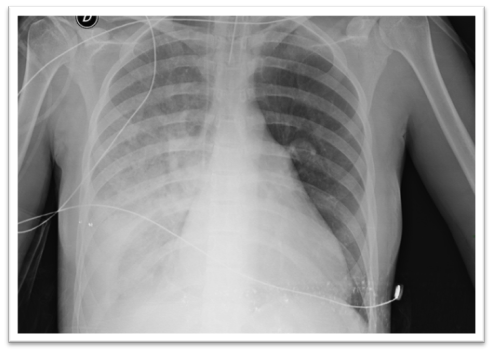

CT angiography of the neck, thorax, and pelvis: Dilation of the main pulmonary artery (33 mm), right pulmonary artery and its branches, a finding suggestive of PH. The left pulmonary artery decreased in calibre, reaching 11 mm, with dilation at the level of its bifurcation in its lobar branches. Enlargement of the right atrium and wall of the right ventricle. No other vascular abnormalities were observed in the remaining explored territories (Figures 2 and 3).

Figure 2

Figure 3

Right pulmonary catheterization: blood pressure 140/70 (mean 90) mm Hg; left ventricle108/6 (mean 10) mmHg; right atrium 10 mmHg; pulmonary artery pressure (PAP) 74/20 (mean 43) mm Hg; right ventricle73/0 (mean 9) mmHg; wedge pressure (WP) 14 mmHg; cardiac index 2.4 L/min/m2; pulmonary vascular resistance 8uW. A volume overload test was performed with 400 ml. No increase in WP or mPAP was observed. A patent dilated right PA was observed, without signs of PE. Hypoplastic left PA with a deficit of distal arborization and absence of vessels to the lower lobe.